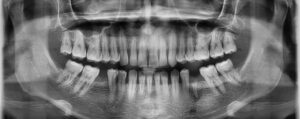

Permite tener una visión general de todas las estructuras dentarias y maxilofaciales en una imagen plana (2D), especial para evaluar evolución dentaria, patología de los maxilares e indispensable en ortodoncia.